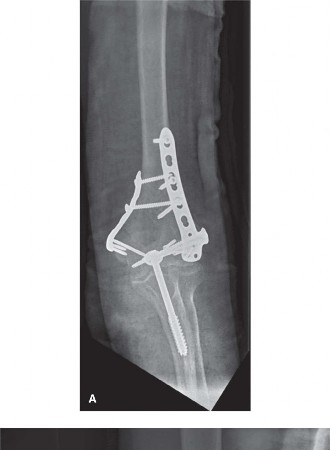

The surgeon elects to use an olecranon osteotomy and performs ORIF using orthogonal plating in combination with several headless compression screws to address the capitellum fracture. The post-op radiographs are shown in Figure 6–12A and B.

Figure 6–12 A–B

The correct answer is (D). It is extremely common to lose some elbow range of motion after elbow fractures, particularly with distal humerus fractures. This loss of motion may be due to a number of variables including articular incongruity, capsular contractures, loose bodies, heterotopic ossification, and/or prominent hardware. The average flexion contracture following ORIF of distal humerus fractures is 20 to 25 degrees, and an expected total arc of motion is 100 to 110 degrees. Symptomatic hardware is common as well, especially with an olecranon fracture or osteotomy. In this case, however, the olecranon osteotomy was fixed with a cancellous screw and washer which requires hardware removal less frequently than other fixation methods such as tension band wiring, where wire back-out is a frequent issue. Another complication, specifically associated with an olecranon osteotomy, is nonunion of the osteotomy site.